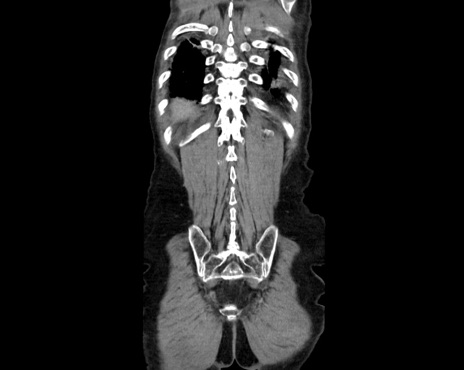

症例26(冠状断像)

【症例】80歳代男性

【主訴】嘔吐

【現病歴】昨晩2回嘔吐あり、今朝になっても嘔吐あり。来院。

【既往歴】胃潰瘍

【身体所見】意識清明、BT 37.6℃、BP 166/95mmHg、HR 100bpm、SpO2 97%、腹部:平坦・軟、腸蠕動音聴取良好、圧痛なし。

【データ】WBC 21900、CRP 1.4